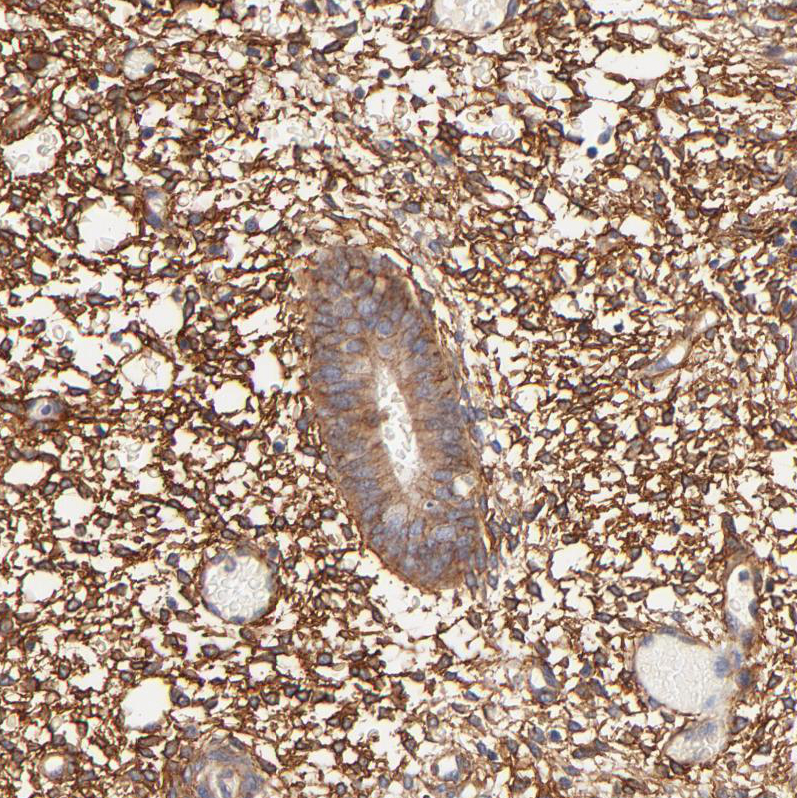

Immunohistochemical staining of human endometrium shows strong membranous positivity in stromal cells.